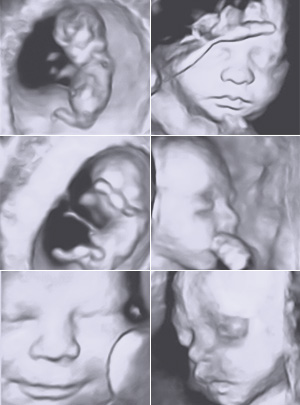

3D/4D Sono